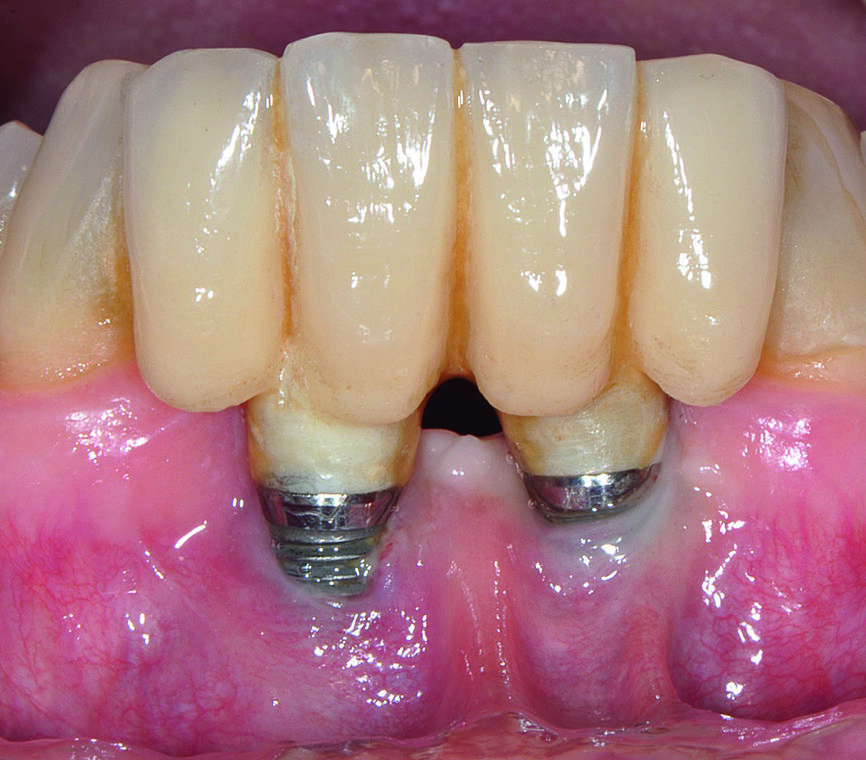

Dans le domaine dentaire, la parodontite est l’une des principales maladies chroniques non transmissibles. Les spécialistes de la parodontologie et les scientifiques internationaux ont élaboré divers principes de prévention des maladies parodontales.2 La péri-implantite est une version du XXIe siècle de la parodontite et sa fréquence s’accroît avec l’augmentation du nombre d’implants posés (Figs. 1–3). Tout comme la parodontite, cet état pathologique est associé au biofilm, mais au lieu de toucher les desmodontes et les tissus osseux, elle se caractérise par une inflammation de la muqueuse péri-implantaire et la perte progressive de l’os de soutien.3 Les préoccupations majeures dans ce problème sont liées au rôle déterminant que peuvent jouer de multiples facteurs de risque incriminés dans l’étiologie4 et l’absence d’un traitement de référence. Les mesures de prévention primaires et secondaires sont réellement importantes pour éviter la survenue d’une mucite et d’une péri-implantite ainsi que les récidives, mais de nombreux détails doivent être pris en considération avant une pose d’implants de façon à minimiser les problèmes iatrogènes. Outre les implants, les solutions prothétiques que peuvent proposer les professionnels de la santé buccodentaire aux patients sont nombreuses et diverses s’il est tenu compte de la situation globale du début jusqu’à la fin. Les implants peuvent ne pas toujours être dans le meilleur intérêt d’un patient. Par conséquent, avant la pose d’un implant, chaque clinicien devrait évaluer non seulement les aspects spécifiques du patient et du site implantaire, mais également les compétences du chirurgien, du chirurgien-dentiste, de l’hygiéniste buccodentaire et du prothésiste dentaire afin de minimiser le risque de péri-implantite dans le futur. Il est nécessaire de procéder à l’examen des points suivants avant la prévention primaire et secondaire, une approche que nous appelons dans notre article, la « Prévention 0 ».

Figs. 1a : Implant en position 14 affecté par une péri-implantite : sondage péri-implantaire avec la couronne prothétique in situ

Fig b : Implant en position 14 affecté par une péri-implantite : sondage péri-implantaire après retrait de la couronne prothétique.